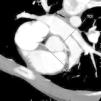

Se muestran las imágenes del árbol coronario que permiten descartar anomalías en esta localización. La figura 1 muestra una proyección axial de máxima intensidad (MIP) de la salida de las arterias coronarias. La figura 2 es una proyección coronal de máxima intensidad (MIP) de la arteria coronaria derecha similar a la proyección oblicua anterior derecha de la angiografía. Las figuras 3 y 4 son reconstrucciones en volume rendering en proyección oblicua anterior izquierda del tronco coronario izquierdo y su bifurcación y de la base del corazón, en la que se visualiza la salida del tronco coronario izquierdo. Se han retirado las venas pulmonares izquierdas. En la estación de trabajo, mediante el análisis avanzado de vasos se puede visualizar un vaso tortuoso o de trayecto curvo en un solo plano tomográfico permitiendo una cuantificación de la lesiones estenóticas. El estudio no detectó anomalía en la anatomía ni estenosis coronaria significativa en el paciente.

Figura 1. Proyección axial de máxima intensidad de la salida de las arterias coronarias. ADA: arteria coronaria derecha; TCI: tronco coronario izquierdo.